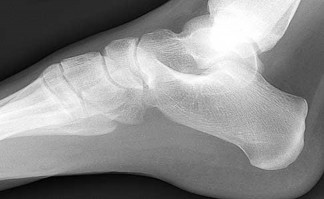

A 30-year-old female sustains a midfoot injury after falling from a horse. Radiographs demonstrate diastasis between the bases of the 1st and 2nd metatarsals. In a normal anatomic state, the native Lisfranc ligament originates and inserts on which two bony structures?

Correct Answer: Lateral aspect of the medial cuneiform to the medial aspect of the base of the 2nd metatarsal

Explanation:

The Lisfranc ligament is a stout, obliquely oriented intra-articular ligament that acts as the primary stabilizer of the second tarsometatarsal joint complex. It connects the lateral aspect of the medial cuneiform to the medial aspect of the base of the second metatarsal. Importantly, there is no direct ligamentous connection between the bases of the first and second metatarsals.